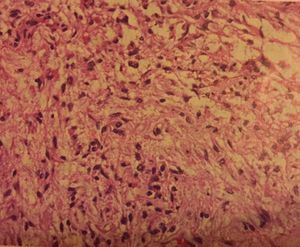

Actually the gland is derived from two embryologically-distinct tissues,and is therefore composed of both neural and glandular tissue. The pattern of staining should reflect the chemical character of intracellular hormone-laden granules within the pituitary cells and should i think show exactly like the histology of the pic.